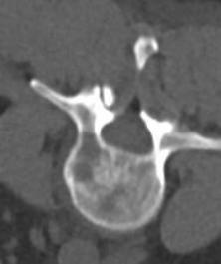

联合骨组织/软组织活检

|

椎体破坏 |

局麻 |

14G骨入路 |

16G TruCut 活检针:Osteolytic bone metastasis from urothel carcinoma |